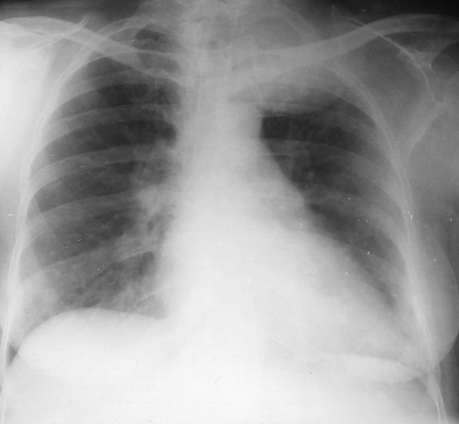

Rx toracică, incidență P-A

DESCRIERE:

la niv. întregului hemitorace drept → opacitate extinsă, nesistematizată, de intensitate mare, omogenă

caracter expansiv → împinge traheea și mediastinul de partea opusă

diafragm deplasat în jos

lărgirea spațiilor intercostale

umplerea spațiului costo-diafragmatic

DX: pleurezie masivă

DD: atelectazie → caracter retractil